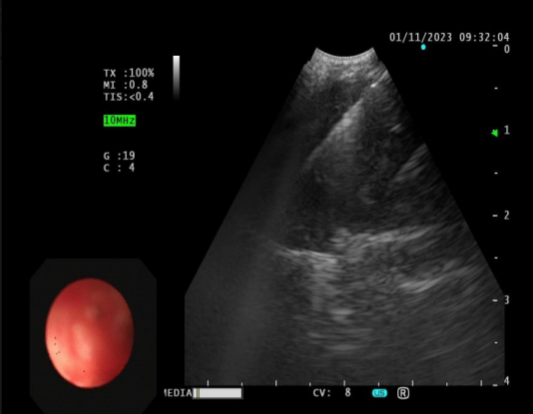

在73岁的王大爷身上,EBUS-TBNA同样发挥了重要作用。患者因胸闷入院,胸部CT显示右肺占位并伴有淋巴结肿大。

诊断结果:小细胞癌

通过对纵隔和肺门淋巴结的活检,EBUS-TBNA能够帮助医生明确癌症的分期,从而指导后续的治疗决策。在活检过程中,医生能够实时观察穿刺针的位置,确保准确性,减少误穿血管的风险。通过获取淋巴结样本,医生能够在不进行侵入性手术的情况下,确认癌症的存在和类型。